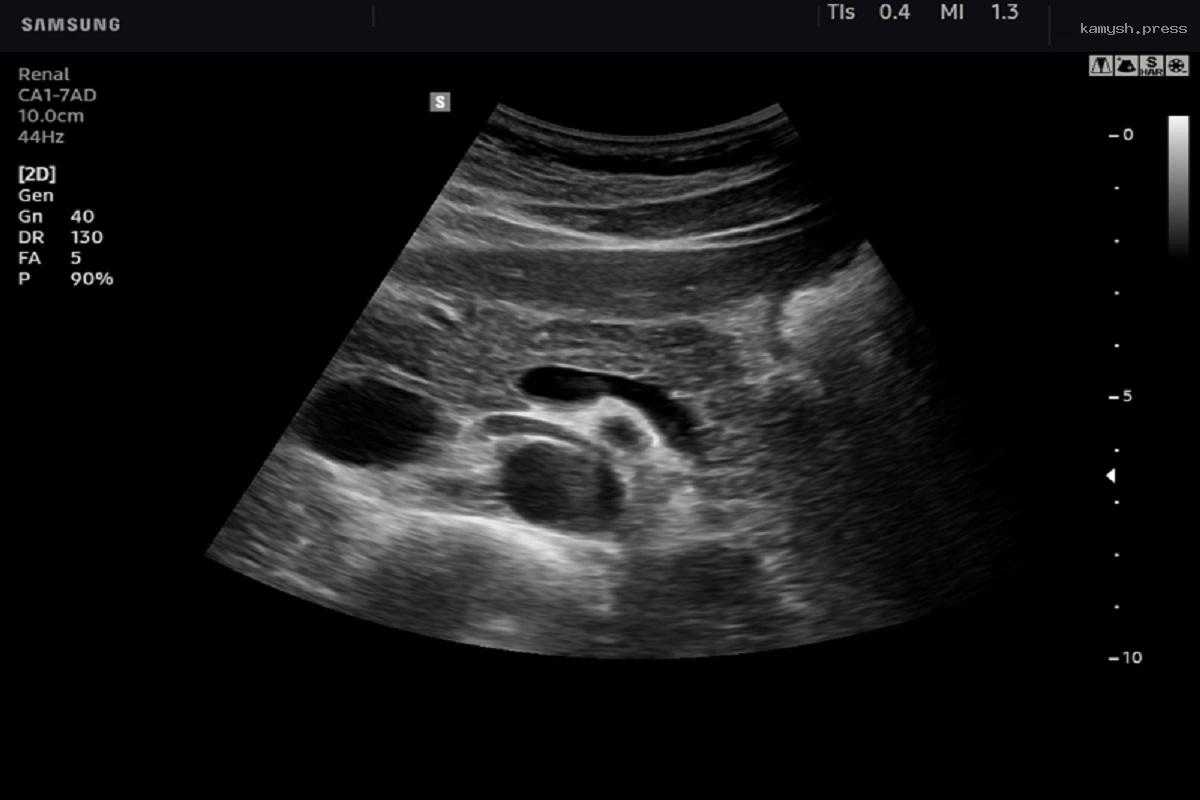

По словам врача-онколога Валерия Егиева, для диагностики рака необходимо провести УЗИ, КТ, МРТ а также сдать анализы на онкомаркеры.

Чтобы диагностировать рак Егиев рекомендует пройти полное обследование, включающее УЗИ, анализ на онкомаркеры, КТ и МРТ.